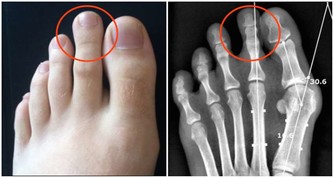

4.預防壞血病,同時對牙齦出血、貧血等都有幫助。